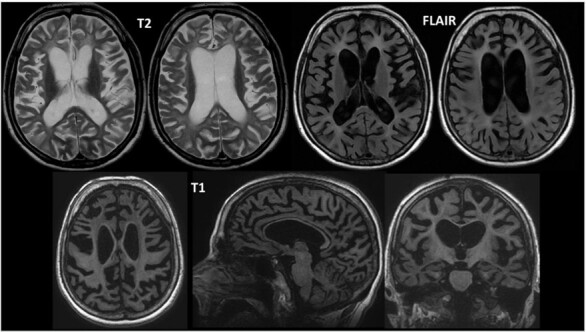

多囊性脂膜性骨发育不良伴硬化性白质脑病(nasu - hakola病)是一种遗传性进行性病理,主要与老年前痴呆和骨结构改变有关。目的:报告两例罕见的兄弟姐妹早发性痴呆综合征的遗传病因治疗,并回顾相关文献。方法:查阅病历、访谈和记录患者所采用的诊断方法。据此,研究人员准备了一份报告,其中包括两名在生命第三个十年开始行为改变的患者,他们在不同的时间出现了类似认知障碍的症状。在美国国家医学图书馆(PubMed)、医学文献分析和在线检索系统(MEDLINE)、拉丁美洲和加勒比卫生科学文献(LILACS)、UpToDate和科学电子在线图书馆(SciELO)数据库中进行书目研究,以进行书目审查。结果:本文报告2例遗传确证的纳苏-哈科拉病临床病例,并复习了相关文献。结论:这些病例说明了老年前痴呆综合征的表现,并强调了充分的诊断和及时治疗的重要性,人性化的多学科随访旨在提高生活质量,以及遗传和家庭咨询。

The polycystic lipomembranous osteodysplasia with sclerosing leukoencephalopathy-Nasu-Hakola disease-is a hereditary and progressive pathology, which is mainly associated with pre-senile dementia and changes in bone architecture.

Results: Two clinical cases with genetic confirmation of Nasu-Hakola disease and a brief literature review were described.